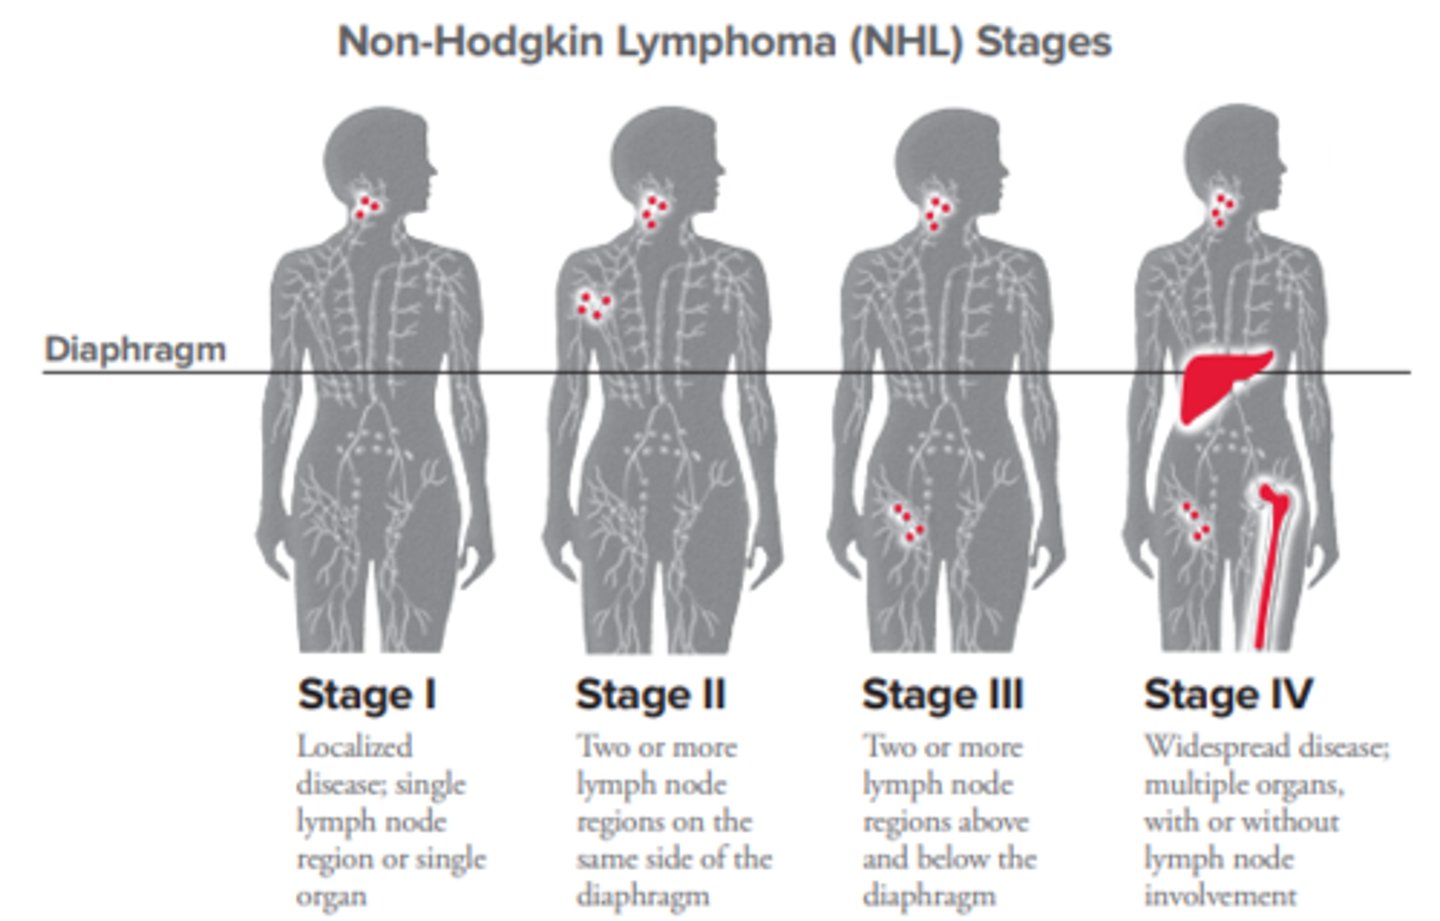

Non-Hodgkin's lymphomas (NHLs)

Definition: Tumor that originates in multiple lymph nodes --> spread to other body tissues

Pathogenesis: B cells OR T cells become malignant

Etiology: Infections, immunosuppression, chemicals

S+S: Painless enlargement of lymph nodes in neck, axilla, or groin, fever, weight loss

Treatment: Chemo, radiation

What ages are most affected by Non-Hodgkin's lymphoma?

Common in the elderly (over 65 yrs)